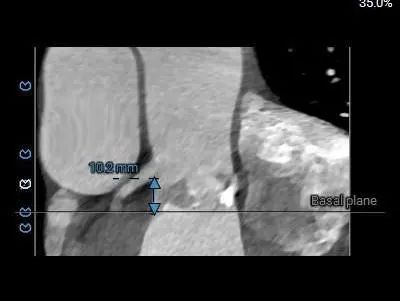

主动脉根部详细情况:

冠脉风险:

RCA & Leaflet

左右冠开口高度稍低,综合瓦氏窦及窦管交界内径综合判断,预估左右侧冠脉阻挡风险适中,术中可根据球扩结果进一步判断,必要时行冠脉保护。